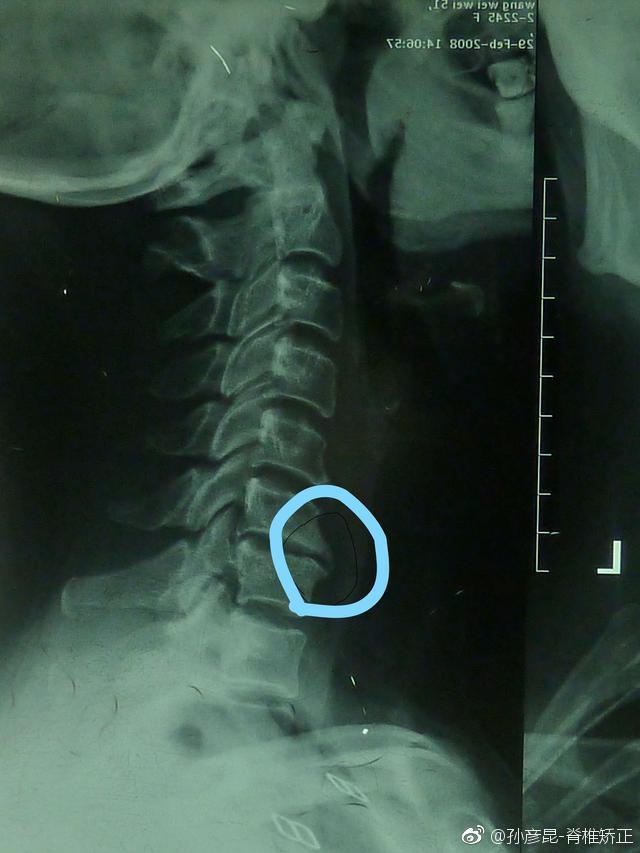

颈椎生理曲度反张:颈椎曲度跟正常人相反,这种人的颈椎是非常严重的,无形中形成了一个被动的低头动作,这时候再去低头就会更累了,这时椎间盘受到的压力就会增加几十倍,颈椎进一步退化,椎间盘突出,骨质增生严重,椎体压缩性骨折,这时候整个颈椎就很严重了,会压迫神经,导致胳膊疼痛、麻木、头晕、头痛、颈椎僵硬疼痛等较严重的症状。只要矫正反张,这些症状都会得到有效治疗。